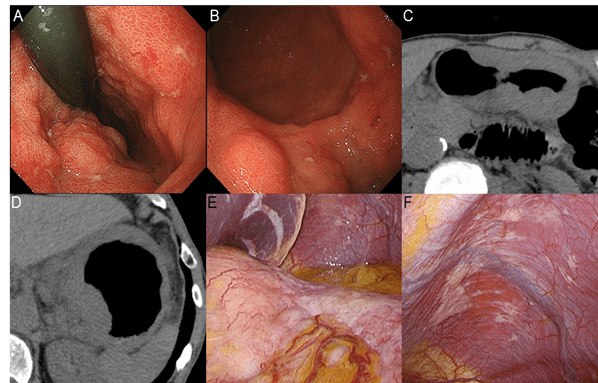

A 68-year-old man was presenting with epigastric pain as the main complaint. He had no remarkable medical history. Physical examination revealed no palpable mass or tenderness in his abdomen with normal bowel sound. Blood tests showed no anemia or other abnormal findings. Esophagogastroduodenoscopy (EGD) revealed EGC and referred to our hospital. Two lesions were identified in the stomach. One was a superficial depressed lesion with redness 35 mm in diameter at the lesser curvature of the upper gastric body (Lesion 1, Figure 1A) and slightly central fold concentrations, where endoscopic ultrasonography showed a diffusely thickened hypoechoic region at the submucosa layer, suggesting submucosal invasion. The biopsy specimen revealed low to moderately differentiated adenocarcinoma. The second lesion was a slightly depressed lesion with erosion 40 mm in diameter at the lesser curvature of the posterior wall of the lower gastric body, suggesting mucosal lesion with ulceration (Lesion 2, Figure 1B). The biopsy specimen revealed moderately differentiated adenocarcinoma. We diagnosed the lesions as synchronous multifocal EGCs, cT1bN0M0, and cStage I, consisting of lesion 1 (U, Less, cT1b) and lesion 2 (M, Less, cT1a) according to the 15th edition of the Japanese classification of gastric carcinoma [4].

Figure 1: Endoscopic findings at the initial examination. Initial esophagogastroduodenoscopy detected two lesions. One lesion (lesion 1) was a superficial depressed lesion with redness, 35 mm in diameter, and central fold concentrations at the lesser curvature of the upper gastric body, suggesting submucosal invasion (A). A biopsy specimen revealed low to moderately differentiated adenocarcinoma. The other lesion (lesion 2) was an erosive lesion, 40 mm in diameter at the lesser curvature of the posterior wall of the lower gastric body, suggesting a mucosal lesion with ulceration (B).